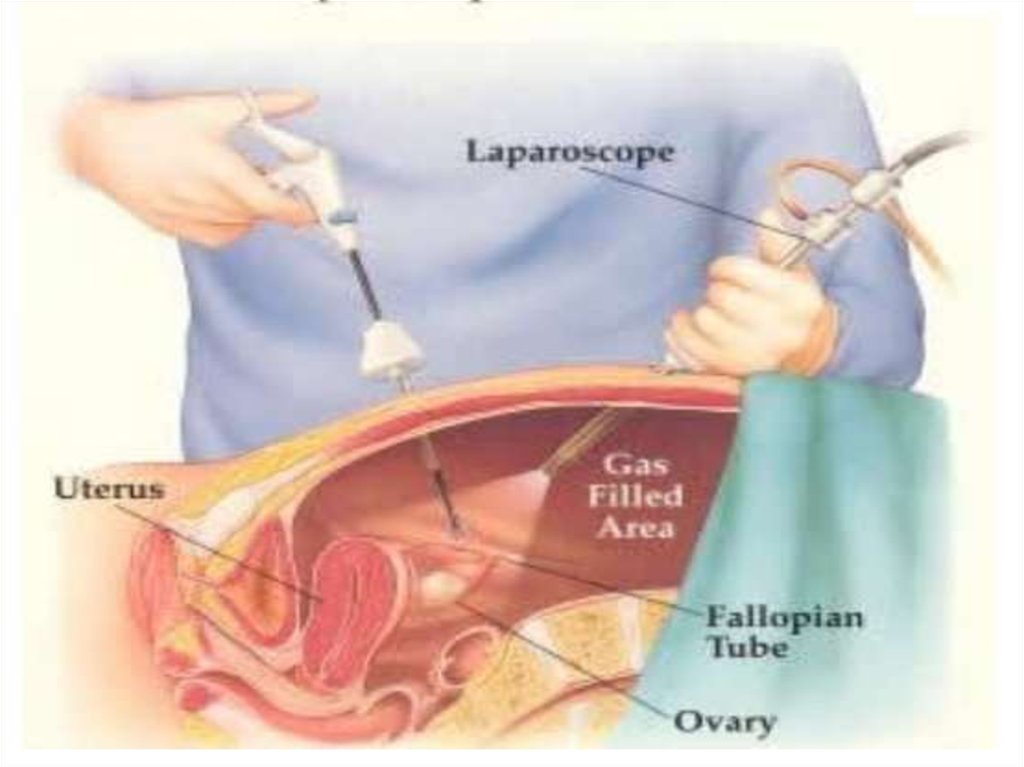

Заблуждения и факты о внутрибрюшной беременности